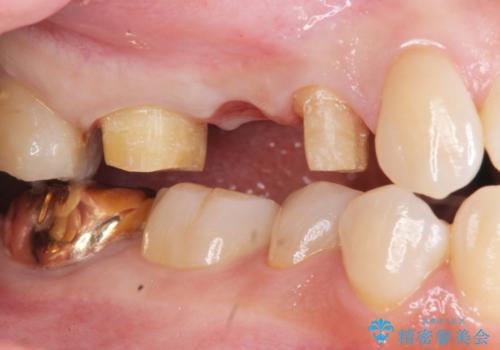

虫歯による歯の喪失 ジルコニアブリッジの製作

- 大きく歯が欠けてしまった虫歯の治療を希望され来院されました。

虫歯による歯の崩壊で歯を残すことが難しかったので抜歯を行い、インプラント・入れ歯ではなくブリッジによる咬合機能の回復を希望されました。